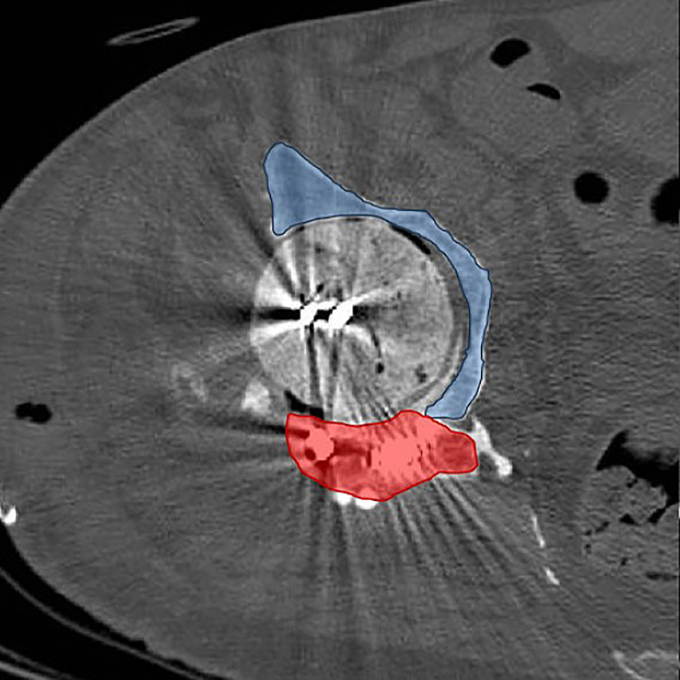

Axial CT image illustrating temporary posterior wall (red) and residual bone stock (blue), explaining multidirectional instability.

Intraoperative fluoroscopic assessment during definitive reconstruction.

During reimplantation, removal of the spacer and prior tectoplasty exposed a Paprosky IIIA acetabular defect. A complete posterior wall deficiency combined with a significant superior acetabular roof defect resulted in translational instability of the trial component in both cranio-caudal and anteroposterior directions. Cranio-caudal stability was achieved using a cranial trabecular titanium augment (TrabecuLink Augments). However, anteroposterior instability persisted.

The decisive step in reconstruction was the mechanical integration of a PPR-type acetabular cage with the trabecular titanium augment. The flanges of the MobileLink PPR were connected directly to the augment using 4.5 mm screws, transforming two independent components into a unified structural construct.

This integrated configuration restored stability in both planes and allowed early full weight-bearing.

On the femoral side, a LINK MP stem combined with an MP 2.0 metaphyseal component (38 mm offset) was implanted. Given the multiply operated hip and compromised soft tissues, a dual mobility articulation (MobileLink Dual Mobility Insert) with ceramic head was chosen to reduce dislocation risk.